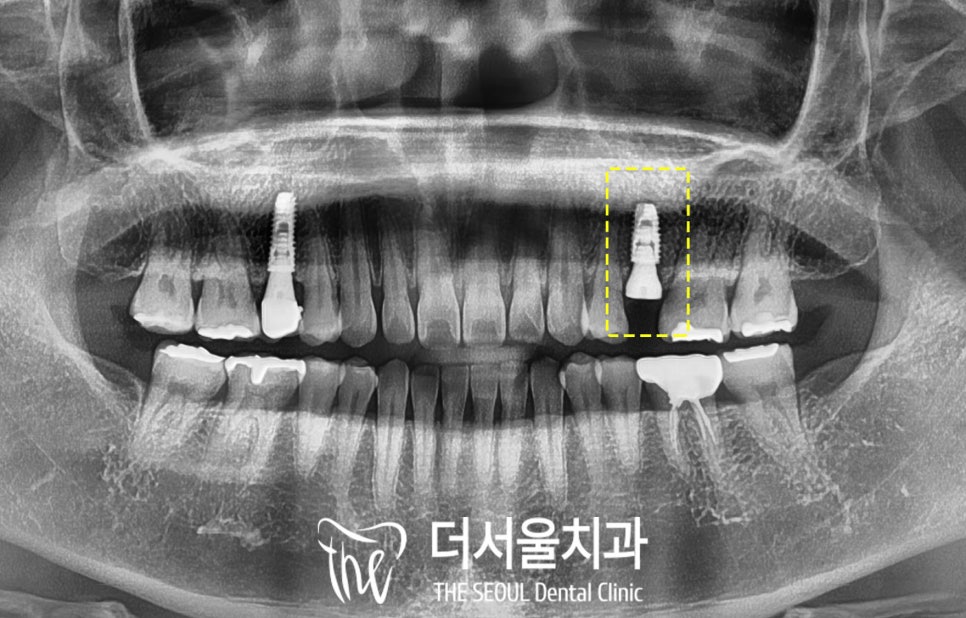

이전에 진료받았던

병원이 사라졌다며

주변 지인의 소개를 받고

더서울에 오신 환자입니다.

검진을 받으러 오셨을 당시

왼쪽 위 신경치료 후 크라운을 씌워놓은

두 번째 작은 어금니(#25) 뿌리 부근에

염증 소견이 있기도 하고,

구강을 살펴보면

크라운과 치관이 떨어져 나간 채로

뿌리만 잇몸에 남아있었습니다.

깨진 양이 많고,

이전에 신경치료를 받았던 이라

이미 수명이 짧아진 채로 약해져있었기에

해당 치아는 발치 후 임플란트를 해야겠습니다.